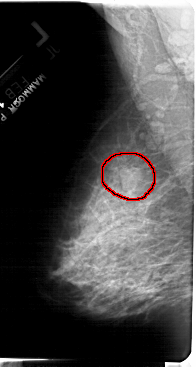

A_1397_1.LEFT_CC

LEFT_CC LINES 5491 PIXELS_PER_LINE 3091 BITS_PER_PIXEL 12 RESOLUTION 43.5 OVERLAY

FILE: A_1397_1.LEFT_CC.OVERLAY

TOTAL_ABNORMALITIES 1

ABNORMALITY 1

LESION_TYPE MASS SHAPE LOBULATED MARGINS OBSCURED

ASSESSMENT 4

SUBTLETY 3

PATHOLOGY BENIGN

TOTAL_OUTLINES 1

BOUNDARY